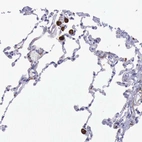

Immunohistochemistry analysis in human lung and cerebral cortex tissues using HPA000272 antibody. Corresponding MSR1 RNA-seq data are presented for the same tissues.